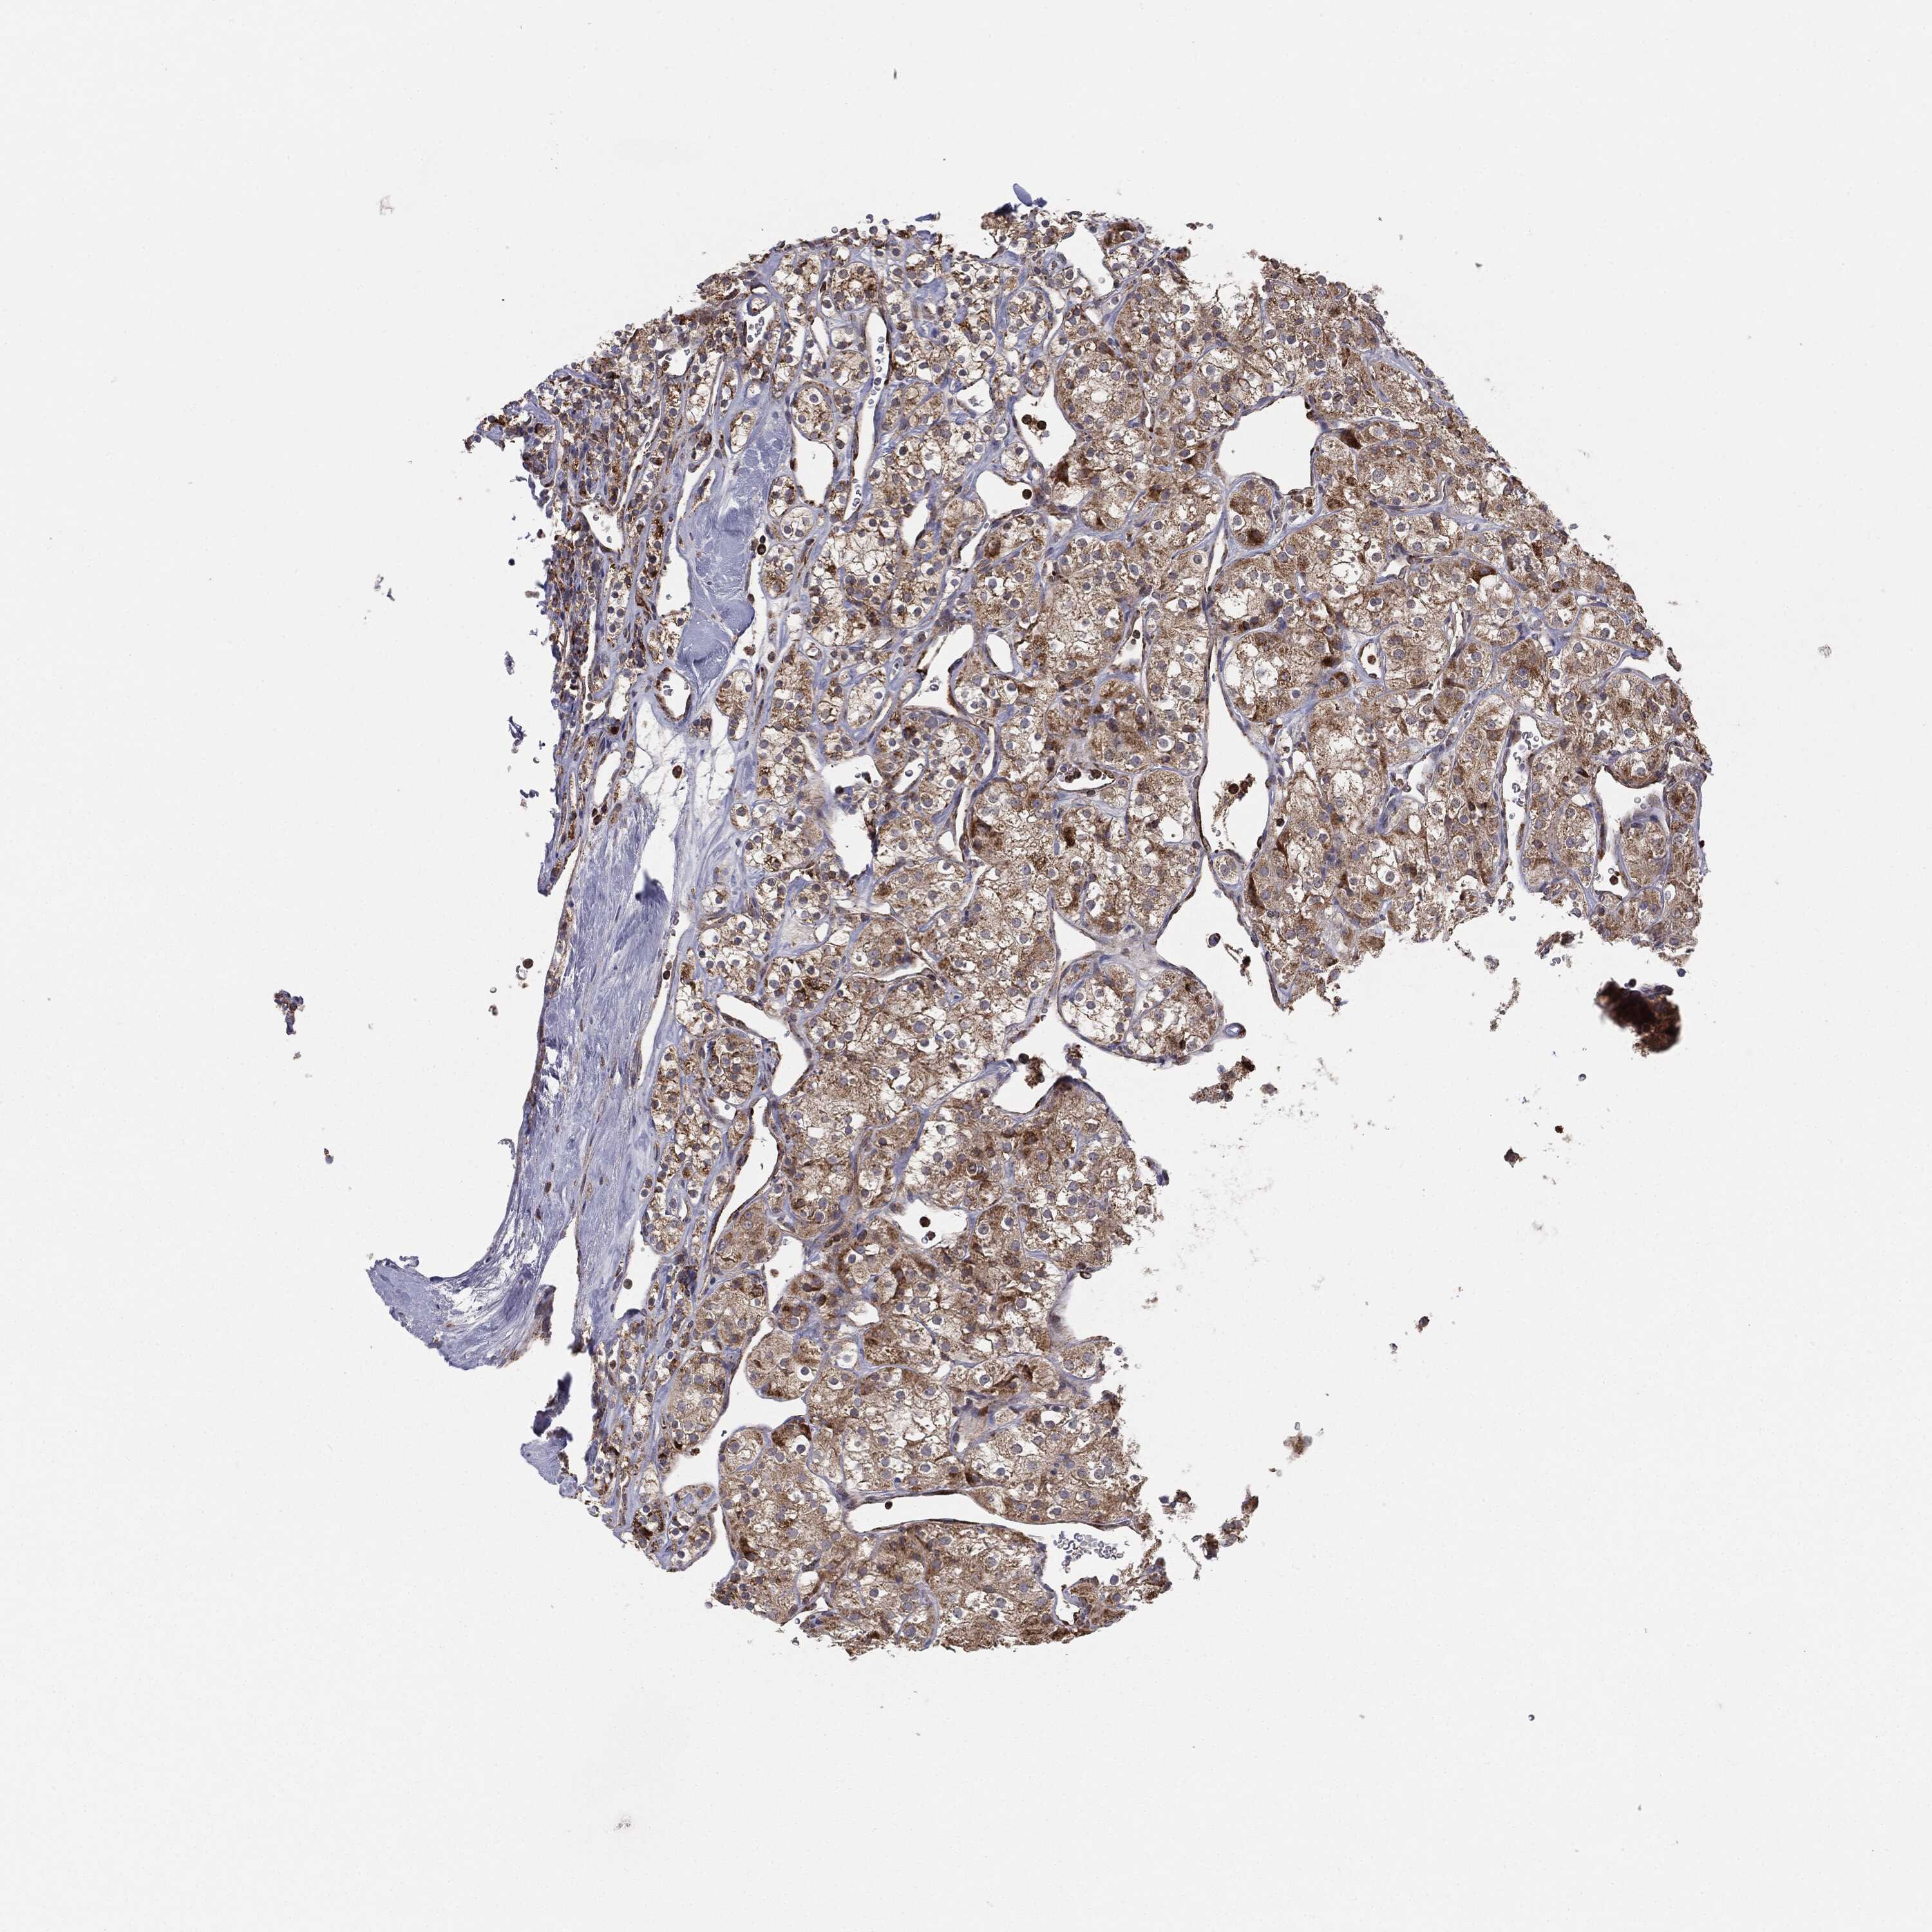

KIDNEY RENAL CLEAR CELL CARCINOMA (TCGA) - Interactive survival scatter ploti

The Survival Scatter plot shows the clinical status (i.e. dead or alive) for all individuals in the patient cohort, based on the same data that underlies the corresponding Kaplan-Meier plots. Patients that are alive at last time for follow-up are shown in blue and patients who have died during the study are shown in red.

The x-axis shows the expression levels (FPKM) of the investigated gene in the tumor tissue at the time of diagnosis. The y-axis shows the follow-up time after diagnosis (years). Both axes are complimented with kernel density curves demonstrating the data density over the axes. The top density plot shows the expression levels (FPKM) distribution among dead (red) and alive patients (blue). The right density plot shows the data density of the survived years of dead patients with high and low expression levels respectively, stratified using the cutoff indicated by the vertical dashed line through the Survival Scatter plot. This cutoff is automatically defined based on the FPKM cutoff that minimizes the p-score. The cutoff can be changed by dragging the vertical line or by entering a cutoff value in the square labeled "Current cut-off".

Under the Survival Scatter plot the p-score landscape (black curve; left axis) is shown together with dead median separation (red curve; right axis). Dead median separation is the difference in median mRNA expression between patients who have died with high and low expression, respectively. It is calculated as follows: median FPKM expression of dead patients with high expression - median FPKM expression of dead patients with low expression. This is intended to aid the user in visually exploring custom cutoffs and the associated p-scores and dead median separation.

Individual patient data is displayed and can be filtered by clicking on one or more of the category buttons on the top of the page. Categories describing expression level and patient information include: high, low, alive, dead, female, male and tumor stages. The scale of the x-axis can be toggled between linear and log-scale by clicking on the "x log" button. Mouse-over function shows TCGA ID, patient information and mRNA expression (FPKM) for each patient.

& Survival analysisi

Kaplan-Meier plots summarize results from analysis of correlation between mRNA expression level and patient survival. Patients were divided based on level of expression into one of the two groups "low" (under cut off) or "high" (over cut off). X-axis shows time for survival (years) and y-axis shows the probability of survival, where 1.0 corresponds to 100 percent.

MTOR is not prognostic in Kidney Renal Clear Cell Carcinoma (TCGA)

: 12.09

Average pTPM 12.2

Number of samples 521